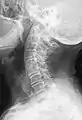

Block vertebrae occur when there is improper segmentation of the vertebrae, leading to parts of or the entire vertebrae being fused. The adjacent vertebrae fuse through their intervertebral discs and also through other intervertebral joints so that it can lead to blocking or stretching of the exiting nerve roots from that segment. It may lead to certain neurological problems depending on the severity of the block. It can increase stress on the inferior and the superior intervertebral joints. It can lead to an abnormal angle in the spine, there are certain syndromes associated with block vertebrae; for example, Klippel–Feil syndrome. The sacrum is a normal block vertebra.

- Block vertebrae of the cervical spine (vertebrae 4 and 5). Probably based on degenerative or inflammatory changes.

- Several congenital block vertebrae in the transition from the thoracic to the lumbar spine and hemivertebrae.

- Congenital block vertebra in the lumbar spine (partial vertebrae 3 and 4). The rear portion of the disc still exists.

- Congenital block vertebra of the lumbar spine. CT volume rendering.